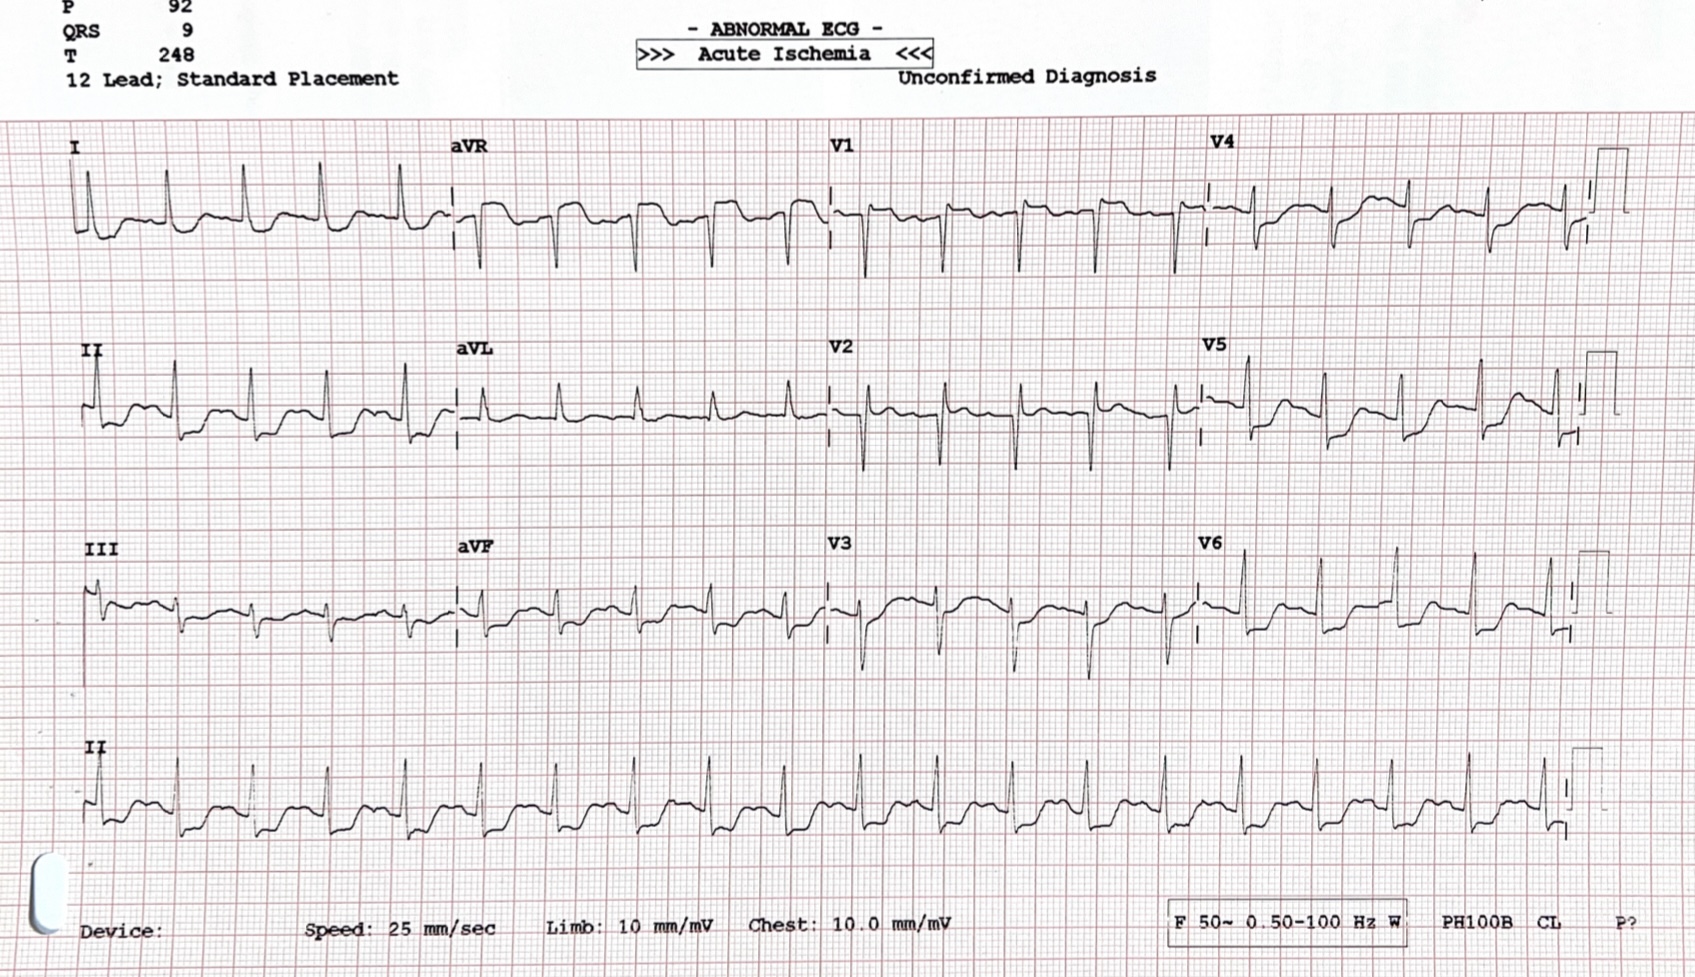

The ECG showed ST elevation in aVR with reciprocal ST depression in leads V4-V6, II, and aVF.